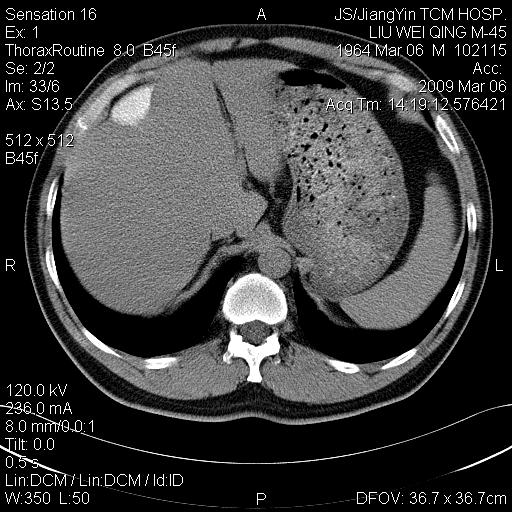

标题: CT18518:胸部扫描时发现肝边缘钙体影。请问是韧带钙化吗? [打印本页]

标题: CT18518:胸部扫描时发现肝边缘钙体影。请问是韧带钙化吗?

没见过。考虑肝内钙化,不象韧带钙化。

考虑肝内右外侧缘两处钙化,原因呢?(血管病变或其它)

考虑肝包膜下陈旧性包裹性积液。

考虑---局限性腹腔积液〔钙乳性〕。    一般多为炎症刺激造成局部钙乳沉着所致。

考虑肝包膜下钙化

考虑肝包膜下钙化.